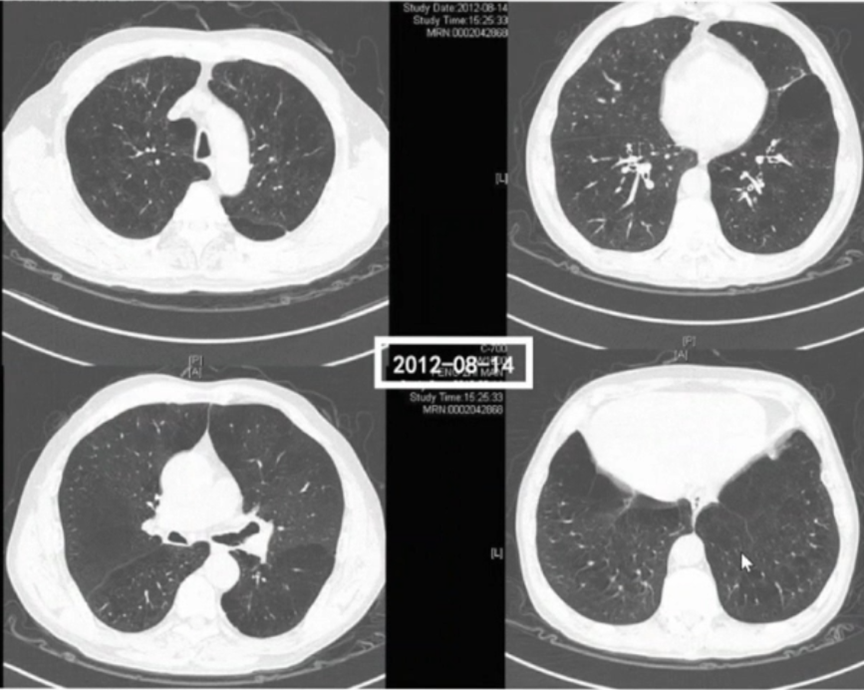

影像学检查:患者入科后第2天行胸部CT检查,结果示:桶状胸,轻度肺气肿,双肺纹理轻微增粗,无明显结节、斑片或大片渗出影,影像学上表现并不明显。

图片

入科第2天行血GM试验,结果回报2.342。痰涂片找到菌丝,PCT 0.05 ng/ml,无明显发热,WBC 8.23×109/L,NEU% 65.7%。持续无创通气,给予莫西沙星、头孢哌酮舒巴坦和伏立康唑治疗。至第4天,患者病情无明显缓解,PaCO2逐渐下降。虽然前期痰涂片找到菌丝,但并未引起重视,因为患者发热症状,血象不是很高,且无侵袭性肺曲霉菌感染的影像学征象。第5天,痰培养提示烟曲霉,给予伏立康唑治疗后,患者喘憋症状无明显好转,多为半卧位或端坐呼吸。

如果存在真菌感染,一定会播散至肺实质,引起影像学进展。但第9天患者胸部CT与之前相比并无明显进展。患者究竟是不是曲霉感染?

回顾该病例的诊治过程:患者做了两次胸部CT,肺内并无明显的曲霉菌感染,通过气管镜检查发现气道内的微小病变,这是曲霉菌侵袭气道黏膜所致。患者有吸入激素和近期短期的全身系统激素使用情况,最终通过病理检查确诊IATB,给予抗真菌药物治疗后,短期内(1周左右)病情得以缓解。1年后随访,患者一般状态较好,病情未再反复,亦未再使用抗真菌药物。